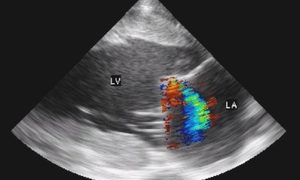

僧帽弁閉鎖不全症(MR)は、左心房と左心室の境界に位置する僧帽弁が逆流をきたす疾患で、運動能力の低下と関連する可能性が最も高い心雑音です。僧帽弁は馬の後天性弁膜疾患の中で2番目に多い場所で、MRは左心房圧を上昇させ、左心房拡張を起こすため、...